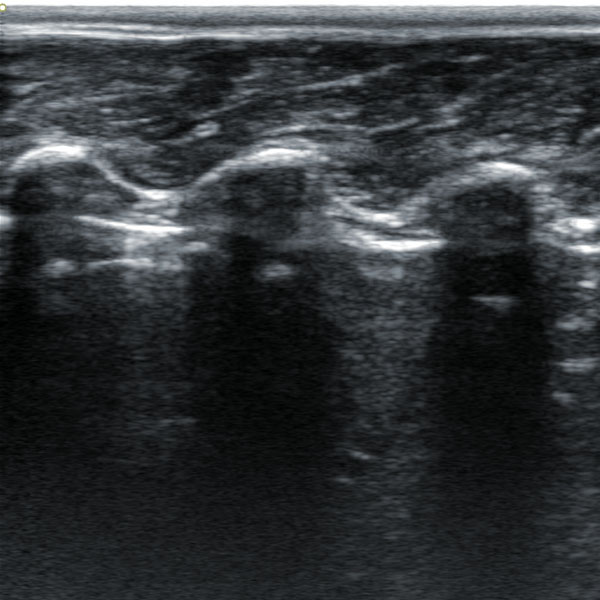

2. Animal back fat eye muscle probe:

2.1. Frequency: 2.5-6MHz 18cm long linear array probe

2.4, Probe scanning depth can reach 30cm

IV. Features of animal backfat eye muscle probe:

1. 18cm long professionally designed backfat eye muscle probe, which can fully test the backfat eye muscles of various animals

2. The probe scanning depth can reach 30cm, which can well present the eye muscles of large animals

3. High-frequency probe and high-quality Doppler color ultrasound images can well identify the measured muscle quality grade